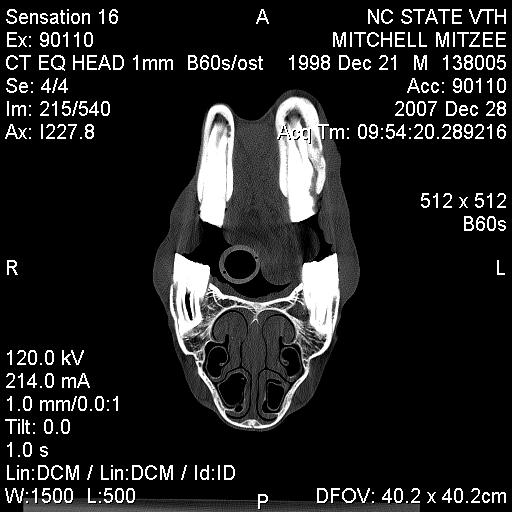

Posted on Sunday, Jun 24, 2007 - 3:39 pm: Greetings Everyone,I have finally received some of Mitzee's xrays, though it appears that I'm missing several... hmmm... Anyway, I thought I would give everyone an update. After two weeks of inpatient care (IV antibiotics, anti-inflamatory agents, a few different wound site I&Ds, several xrays and another fistulogram, etc...), she was discharged on 6/7/7. The final fistulogram showed NO evidence that the draining sinus tract communicated with the adjacent tooth root (4th premolar), but, rather, seemed to travel to the empty alveolar socket of her previous surgical site (the removed 3rd premolar). I had decided I did not want to attempt to manage her on my own, so I arranged to board her and Rorie at a facility owned by an equine vet, kind of like a lay up hospital situation... She's been getting daily assessment and care of her wound, the barn has a great fly control system and, so far, she usually goes out at night and stays in during the hot day. Plus, when she and Rorie are out, they're with other mare/foal pairs and that's a nice bonus for Rorie. Mitzee's eating well, her weight is good, and her activity is normal. And, though tissue healing is occurring, significant swelling of her left submandibular area persists and there are two remaining tracts that drain purulent material, though it is less than previously observed. I have decided to see how things go for awhile and "embrace" this conservative approach... clearly, the surgeon was not interested in pursuing more surgery at the time of her discharge, though when I corresponded with him recently (and showed the same pictures I am posting below) he suggested we get a CT scan. Of course, a CT scan appears to require general anesthesia and I would have to take her to a larger referral, probably academic, center. Based on where I am in VA, the closest facilities are NC State in Raleigh, NC, Marion duPont Scott in Leesburg, VA, or VA Tech in Blacksburg, VA... I do still worry that there's something "left behind" in the wound, perhaps a necrotic bone fragment???, that is continuing to feed this low level infection... At this point in time, she is almost 6 weeks postop from her initial surgery to remove premolar #3... Rorie was 8 weeks old last Tuesday... What does everyone think???? Thanks! Martha

Posted on Tuesday, Jan 1, 2008 - 11:08 pm: Hey Everyone,Sorry for the delay in posting the images... Mitzee was discharged on Sunday (POD 2) and I DrOve down to NC, picked her up, and travelled back to VA in the worst pouring down rain (not complaining, we still do have DrOught conditions a bit...) Anyway, I was on call the next day (New Years eve) and had a killer night, so I am still kinda brain dead today... I've managed to crash my laptop several times with the disc I was given at NC State... just wondering if it has anything to do with my new laptop OS, Vista, but now, finally, I've managed to load some of the study pictures onto my old laptop (hopefully the keyboard won't quit like it did this summer). The plain xray is not great... possibly me altering it in the download process??? Anyway, it is a lateral so you see both sides of the jaw and you have to focus on the near structures (the left side), not the far ones (the right side); basically, it shows distortion of the the left lower premolar #2, which has occurred following removal of #3 last May, and compensatory changes in the left upper arcade (see the big ramp/points above). The few CT views I've uploaded show extensive bony proliferation and periosteal reaction of the left hemimandible, an absent left lower 3rd premolar tooth, as well as some radioopaque densities below this area, presumed to be ?tooth fragments or cement debris following the previous surgery; there is one particular linear density located in the center of this area that was felt to represent a possible "sequestrum" and was removed... also, you can see a radiolucent tract that exits the lower portion of the left hemimandible below the empty alveolar area of the absent 3rd premolar. A lytic lesion is seen associated with the lateral aspect of left lower 4th premolar near the gingival margin and another draining tract travels between this front/rostral portion of the left lower 4th premolar tooth and the lateral aspect of the mandible; my discharge papers state that the CT findings "are consistent with peridontal abscessation and a draining tract", however the surgeon believes the root and pulp of the left lower 4th premolar tooth are still healthy, so we may have a ?50/50 chance of saving that tooth. I have also attached a few other pictures of Mitzee undergoing her CT scan under general anesthesia, her recovery from GA, and a view of the her face following the surgery where the diseased areas were debrided. Her discharge papers note the final diagnosis as "chronic osteomyelitis of the left mandible and peridontal disease adjacent to left mandibular premolar tooth #4". I'll keep everyone posted on her recovery. Thanks!!! Martha

Posted on Monday, Jan 7, 2008 - 4:56 pm: O.K., I am going to try and load the CT images again... please refer to my descriptions of them above. Also, the surgeon from NC State called me today and reported the results of the cultures taken during surgery; Mitzee has grown two types of anaerobic, gram negative rod bacteria, a Prevotella "species" and Fusobacterium nucleatum. He said that he had not had a Prevotella isolated from equines in the past, but that the Fusobacterium is a common oral bacteria in a number of species.... Now, the plan had been for Mitzee to receive two weeks of postop antibiotics, trimethoprim/sulfamethoxazole (Bactrim DS) and when I brought her home on POD#2, I was able to give her the PM dose by syringing paste directly into her mouth (she did protest a little); for the next 24 hours, I was on call and during my absence the barn staff failed miserably in getting any drug into her! I certainly didn't want any of the barn staff to sustain injuries, nor did I want Mitzee to be hurt (apparently, she got into her rearing mode...), so I spoke with the surgeon then and he said I could forego her oral antibiotics (afterall, the surgical debridement was the "definitive" therapy!). Today, he mentioned that metronidazole (Flagyl) was the typical antibiotic for anaerobes, but that horses tolerate it even less than the Bactrim she had been on... so, since he felt good about the debridement, we are not treating her with antibiotics. The plan is to (as long as she looks good "clinically") take her back to Raleigh in about 4 weeks so he can examine her oropharynx and HOPEFULLY see that her orocutaneous fistula is HEALED and that the left lower premolar #4 is still O.K.!!! I'll keep everyone posted!Martha P.S. Keep in mind, when looking at the scans below, you are looking at a "cross-section" or axial image of the head, UPSIDE down... remember that she was laying on her backside to undergo the scan... also, the right side of the image is Mitzee's left side... notice the dramatic difference between the two sides, i.e., each hemimandible...